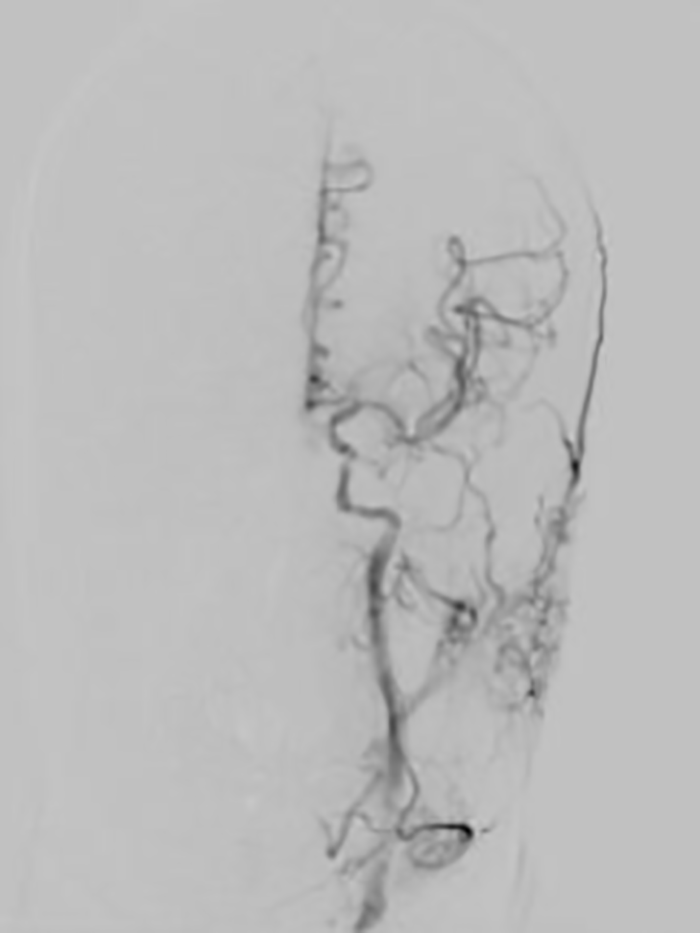

▲患者脑血管造影提示左侧颈内动脉C1段次全闭塞及左侧大脑中动脉M1段闭塞